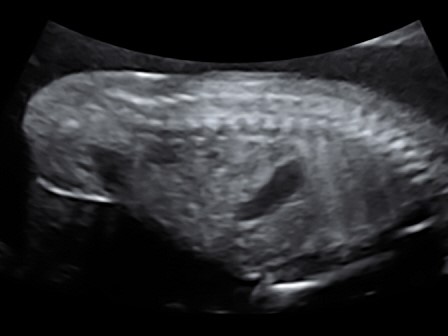

Ultraschall-Galerie